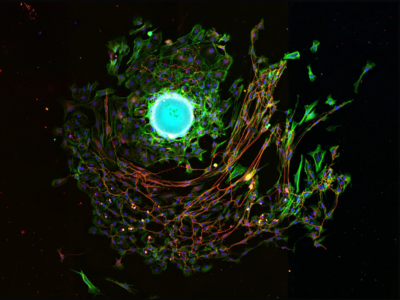

No 7 | Culture de prélèvement exaltée